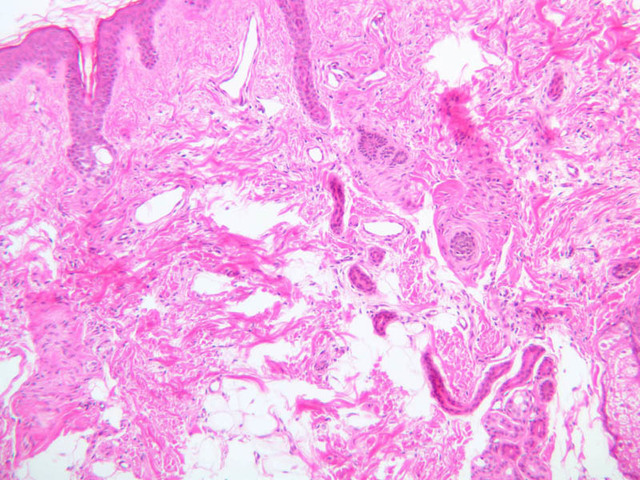

For general orientation, note that skin has two components, epidermis (a stratified squamous epithelium) and dermis (a connective tissue layer beneath the epidermis). Epidermal ridges project into the dermis, enclosing between them the highly vascular dermal papillae. Beneath the dermis lies the subcutaneous tissue, a loose layer of connective tissue, fat, blood vessels, and nerves. The skin appendages are situated partially in the dermis and partially in the subcutaneous layer. The skin consists primarily of two cell types; a keratin-producing epithelial cell (keratinocytes) and a pigment cell of neural crest origin (melanocyte). Langerhans cells are also present. These are believed to be antigen presenting cells of the epidermis. The keratinocytes exhibit morphological and functional stratification from base to surface of the epithelium and thus provide a basis for distinguishing several layers of the epidermis.

Examine slide A-50 (fingertip, H&E [2.5x, 10x-labeled, 20x, 40x-labeled] [20x, 40x] [10x, 20x, 40x] [20x, 20x, 40x]), and study the morphology of five layers of thick skin. The deepest part of the epidermis comprises the stratum basale which provides the cells required for continual renewal of the epidermis. This stratum is composed of a single layer of columnar or cuboidal epithelial cells attached to the basement membrane.

Superficial to the stratum basale is a multi-cellular layer known as the stratum spinosum, consisting of polyhedral cells that have a "prickly" or spiny appearance (A-50, langerhans cells [10x, 20x-labeled, 40x-labeled] [40x, 40x-labeled, 40x, 40x-labeled]; A- 48, abdominal skin, H&E [10x, 20x, 40x] [40x, 40x, 40x, 40x]). The spiny cells are separated by intercellular spaces that are bridged at numerous points by cytoplasmic processes, which in turn are bound together by desmosomes. The cytoplasmic processes projecting on all sides from the cells give them the spiny appearance to which the name refers. These are best seen under high power. Langerhans cells can also be found in this layer.

Superficial to the stratum spinosum is a layer of flattened cells with coarse, deeply-stained cytoplasmic granules, the stratum granulosum (slide A-50 [40x] [40x, 40x] [40x-labeled, 40x, 40x]). These are keratohyalin granules and evidently represent a stage in the keratinization of the epidermal cells. Note that the nuclei of the more superficial granular cells appear dense and pyknotic, foreshadowing their disintegration and the resultant death of the cells.

The stratum lucidum is often considered to be a subdivision of the stratum corneum. This layer is evident only in thick (glaborous) skin. It appears as a clear band beneath the stratum corneum. Cells of the stratum lucidum are well advanced in the process of keratinization. Consequently, the nucleus and many of the cytoplasmic organelles become disrupted and disappear as the cells become filled with the intracellular protein keratin. In many specimens, there is a separation artifact at this point. The outermost layer of the epidermis is called the stratum corneum and is composed of fully cornified (keratinized) remnants of epithelial cells ([40x]). It has a basketweave appearance. The close union of the resulting scales with each other, and their content of insoluble protein and extracellular lipids, provides a barrier to diffusion between the body and its external environment.

The dermis (glands, nerves, blood vessels, collagen, elastic fibers, ground substance-hyaluronic acid and mucopolysaccharides, fibroblasts, macrophages) of the skin is composed of connective tissue beneath the epidermis, and can be divided into two parts, a papillary layer and a reticular layer (A-48 [2.5x, 10x-labeled, 10x]). The papillary layer is the more superficial of the two; it projects up into the epidermis. The boundary between the papillary layer and the reticular layer is not distinct. Examine and compare the dermis in slides A-48 ([2.5x, 10x, 20x, 40x-labeled] [10x-labeled]) and A-50 ([2.5x, 10x, 20x]). Locate glands, nerves, blood vessels, collagen, elastic fibers, ground substance, fibroblasts, and macrophages. The fibers in the papillary layer are much finer than in the reticular layer, where their cross-lacing produces the network from which the name is derived.